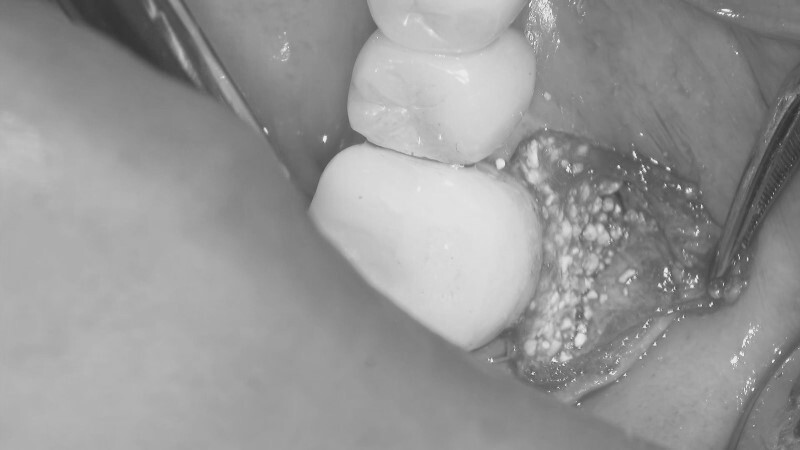

| 主訴 | 歯が折れたため来院。 |

| 治療内容 | 抜歯とともにソケットプリザベーション(歯槽骨再生療法)を行い、歯槽骨の再生を行う。その後にインプラントの埋入処置を行いました。 |

| 治療費 | ソケットプリザベーション:55,000円(税込、オプション別) オプション(エムドゲイン+ベリプラスト):49,500円(税込) インプラント埋入処置:418,000円(税込、埋入~上部構造含め) |

| 治療期間 | 9ヶ月 |

| 治療回数 | 10回 |

| 想定されたリスク | 再生療法を行っても、骨に置換されない場合もあり、その場合は追加的な処置もしくはインプラント埋入自体を断念しなければならない可能性もありました。 |